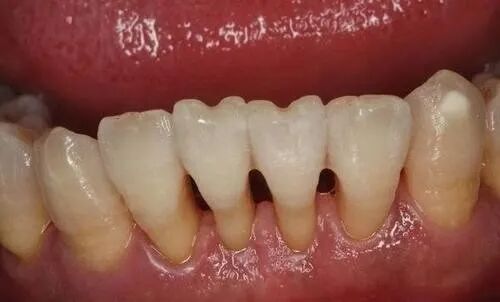

这是临床上最常见的牙龈退缩原因。许多主动来牙周科就诊的患者都有相关主诉:牙缝越来越大、牙齿之间有黑三角、吃东西塞牙、牙齿变长、牙根发酸……虽然最终经过了一系列的牙周治疗之后,关于出血、疼痛、一部分的牙齿松动症状都会不同程度好转,但唯独这一类炎症引起的牙龈退缩几乎是无法逆转的,甚至在大多数的时候,肉眼可见的牙龈退缩情况,由于结石的去除和牙龈红肿的退却,反而会变得更加惨不忍睹。

牙周炎

牙周炎引起牙龈退缩